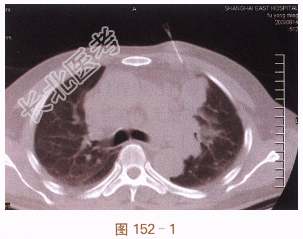

二、影像学资料

常规CT扫描定位(见图152-1),注射器针头扫描确认位置与进针角度。穿刺活检针达病灶边缘,再次扫描确认位置与角度(见图152-2)。行切割活检,取出病理组织(见图152-3)。